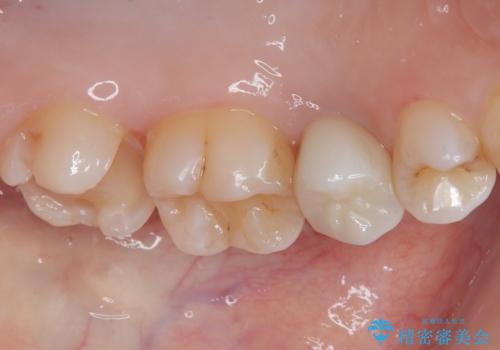

ゴールドインレー(PGAインレー)はセラミックインレーと比べ、歯の切削量が少なく、適合性が著しくいいことが特徴です。上顎の奥歯は見えないので機能面でゴールドインレー、ゴールドクラウンはおすすめです。

違和感がないと喜んでいただきました。